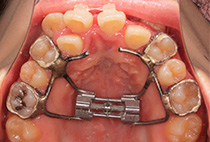

インビザライン、急速拡大装置(MSEⅡ)

ガタガタの歯並びや虫歯になりやすいことが気になっていました。特に上顎は幅が小さく2本の小臼歯抜歯を行ってもスペースが足りず、歯茎に負担のかかる状態でした。

小さすぎる上顎を縫合線から拡大し、歯が並ぶスペースとリップサポートを改善する治療計画を立てました。

急速拡大で上顎の骨を作る。